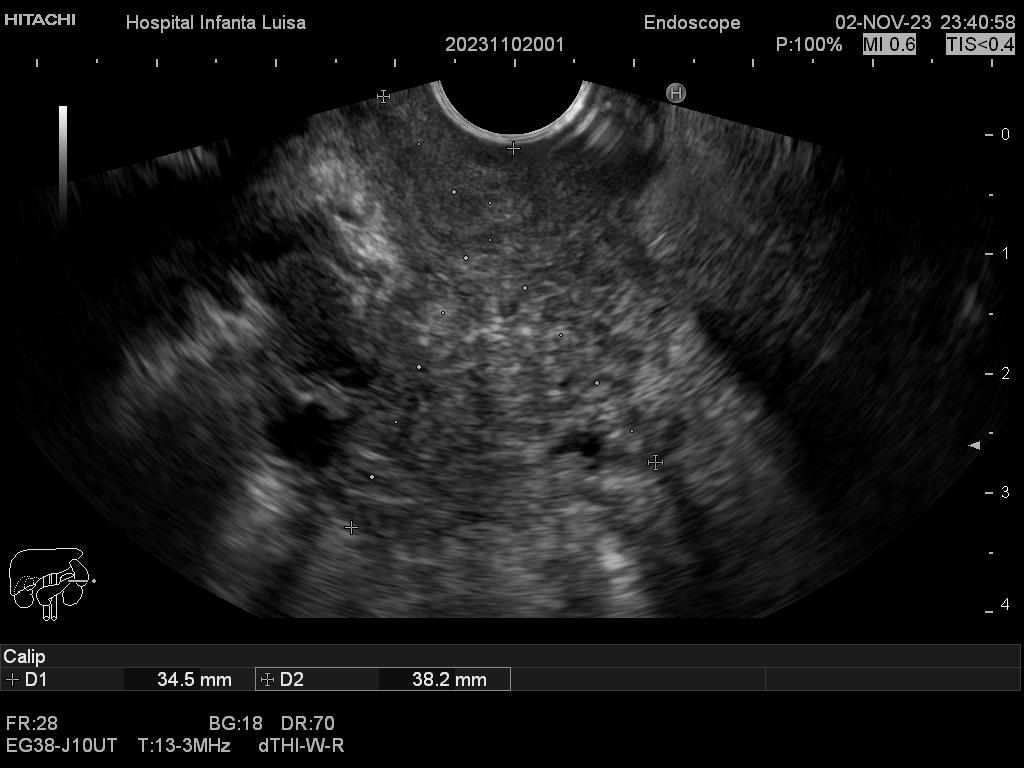

La Ecoendoscopia o Ultrasonografía endoscópica (USE) consiste en la exploración del tracto digestivo superior (principalmente), o de los últimos centímetros del tracto digestivo inferior (recto, generalmente), con un tipo de endoscopio especial que se llama ecoendoscopio.

La Ecoendoscopia, como su nombre indica, combina dos tipos de técnicas: la endoscopia y la ecografía, pues nos aporta simultáneamente una visión endoscópica (similar, aunque no igual, a la alcanzada con el gastroscopio y el colonoscopio) y ecográfica, que permite la visualización y estudio de las estructuras que quedan por fuera y están en contacto con la pared del esófago, estómago, duodeno o colon.

Mediante dicha exploración se explora minuciosamente los tramos mencionados, permitiendo valorar distintas patologías como lesiones propias de la pared de estos órganos (determinado su profundidad y extensión), o lesiones que quedan en órganos anexos, pero por fuera, de ahí la importancia de la visualización ecográfica, como páncreas, mediastino, hígado, diferentes adenopatías o masas indeterminadas previamente, entre otros.

Igualmente, es una técnica básica hoy día en el estudio de todo tipo de lesiones pancreáticas, en la determinación de formaciones subepiteliales esofágicas, gástricas (más frecuentes) o duodenales, o en el estadiaje de patología tumoral a estos niveles. La Ecoendoscopia permite la toma de biopsias a estos niveles, con control endoscópico y ecográfico, siendo una técnica de gran rentabilidad diagnóstica y seguridad.